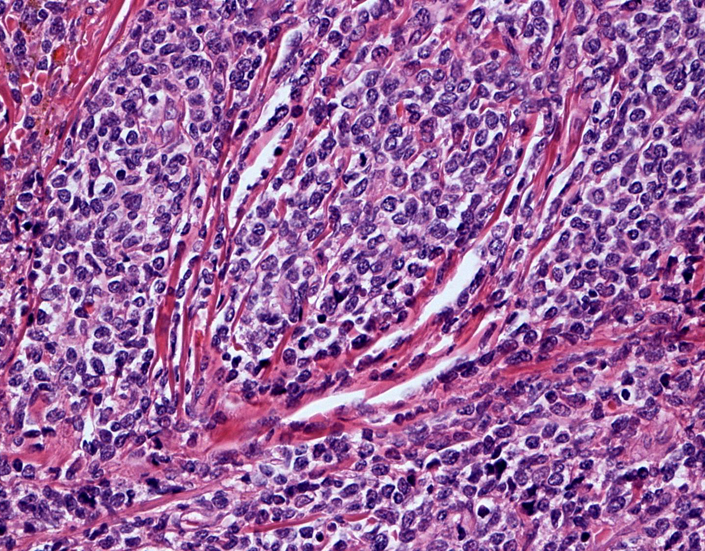

罹患リンパ節の基本構造は消失し腫瘍細胞のびまん性増殖で置換されている。非腫瘍性の小リンパ球(CD3+, CD4/8+)が濾胞様に散在して残る(Fig.01)。不整型または類円形の明るい核をもつmedium-sizeのリンパ球様細胞が密に増殖している。細胞質は乏しい(Fig.02)。CD68陽性macrophageが多く混在する部分が認められた。

Fig03, Fig04は腫瘍細胞の拡大像。大型異型細胞の出現が認められる。腫瘍細胞はCD4+, CD56+, CD123+